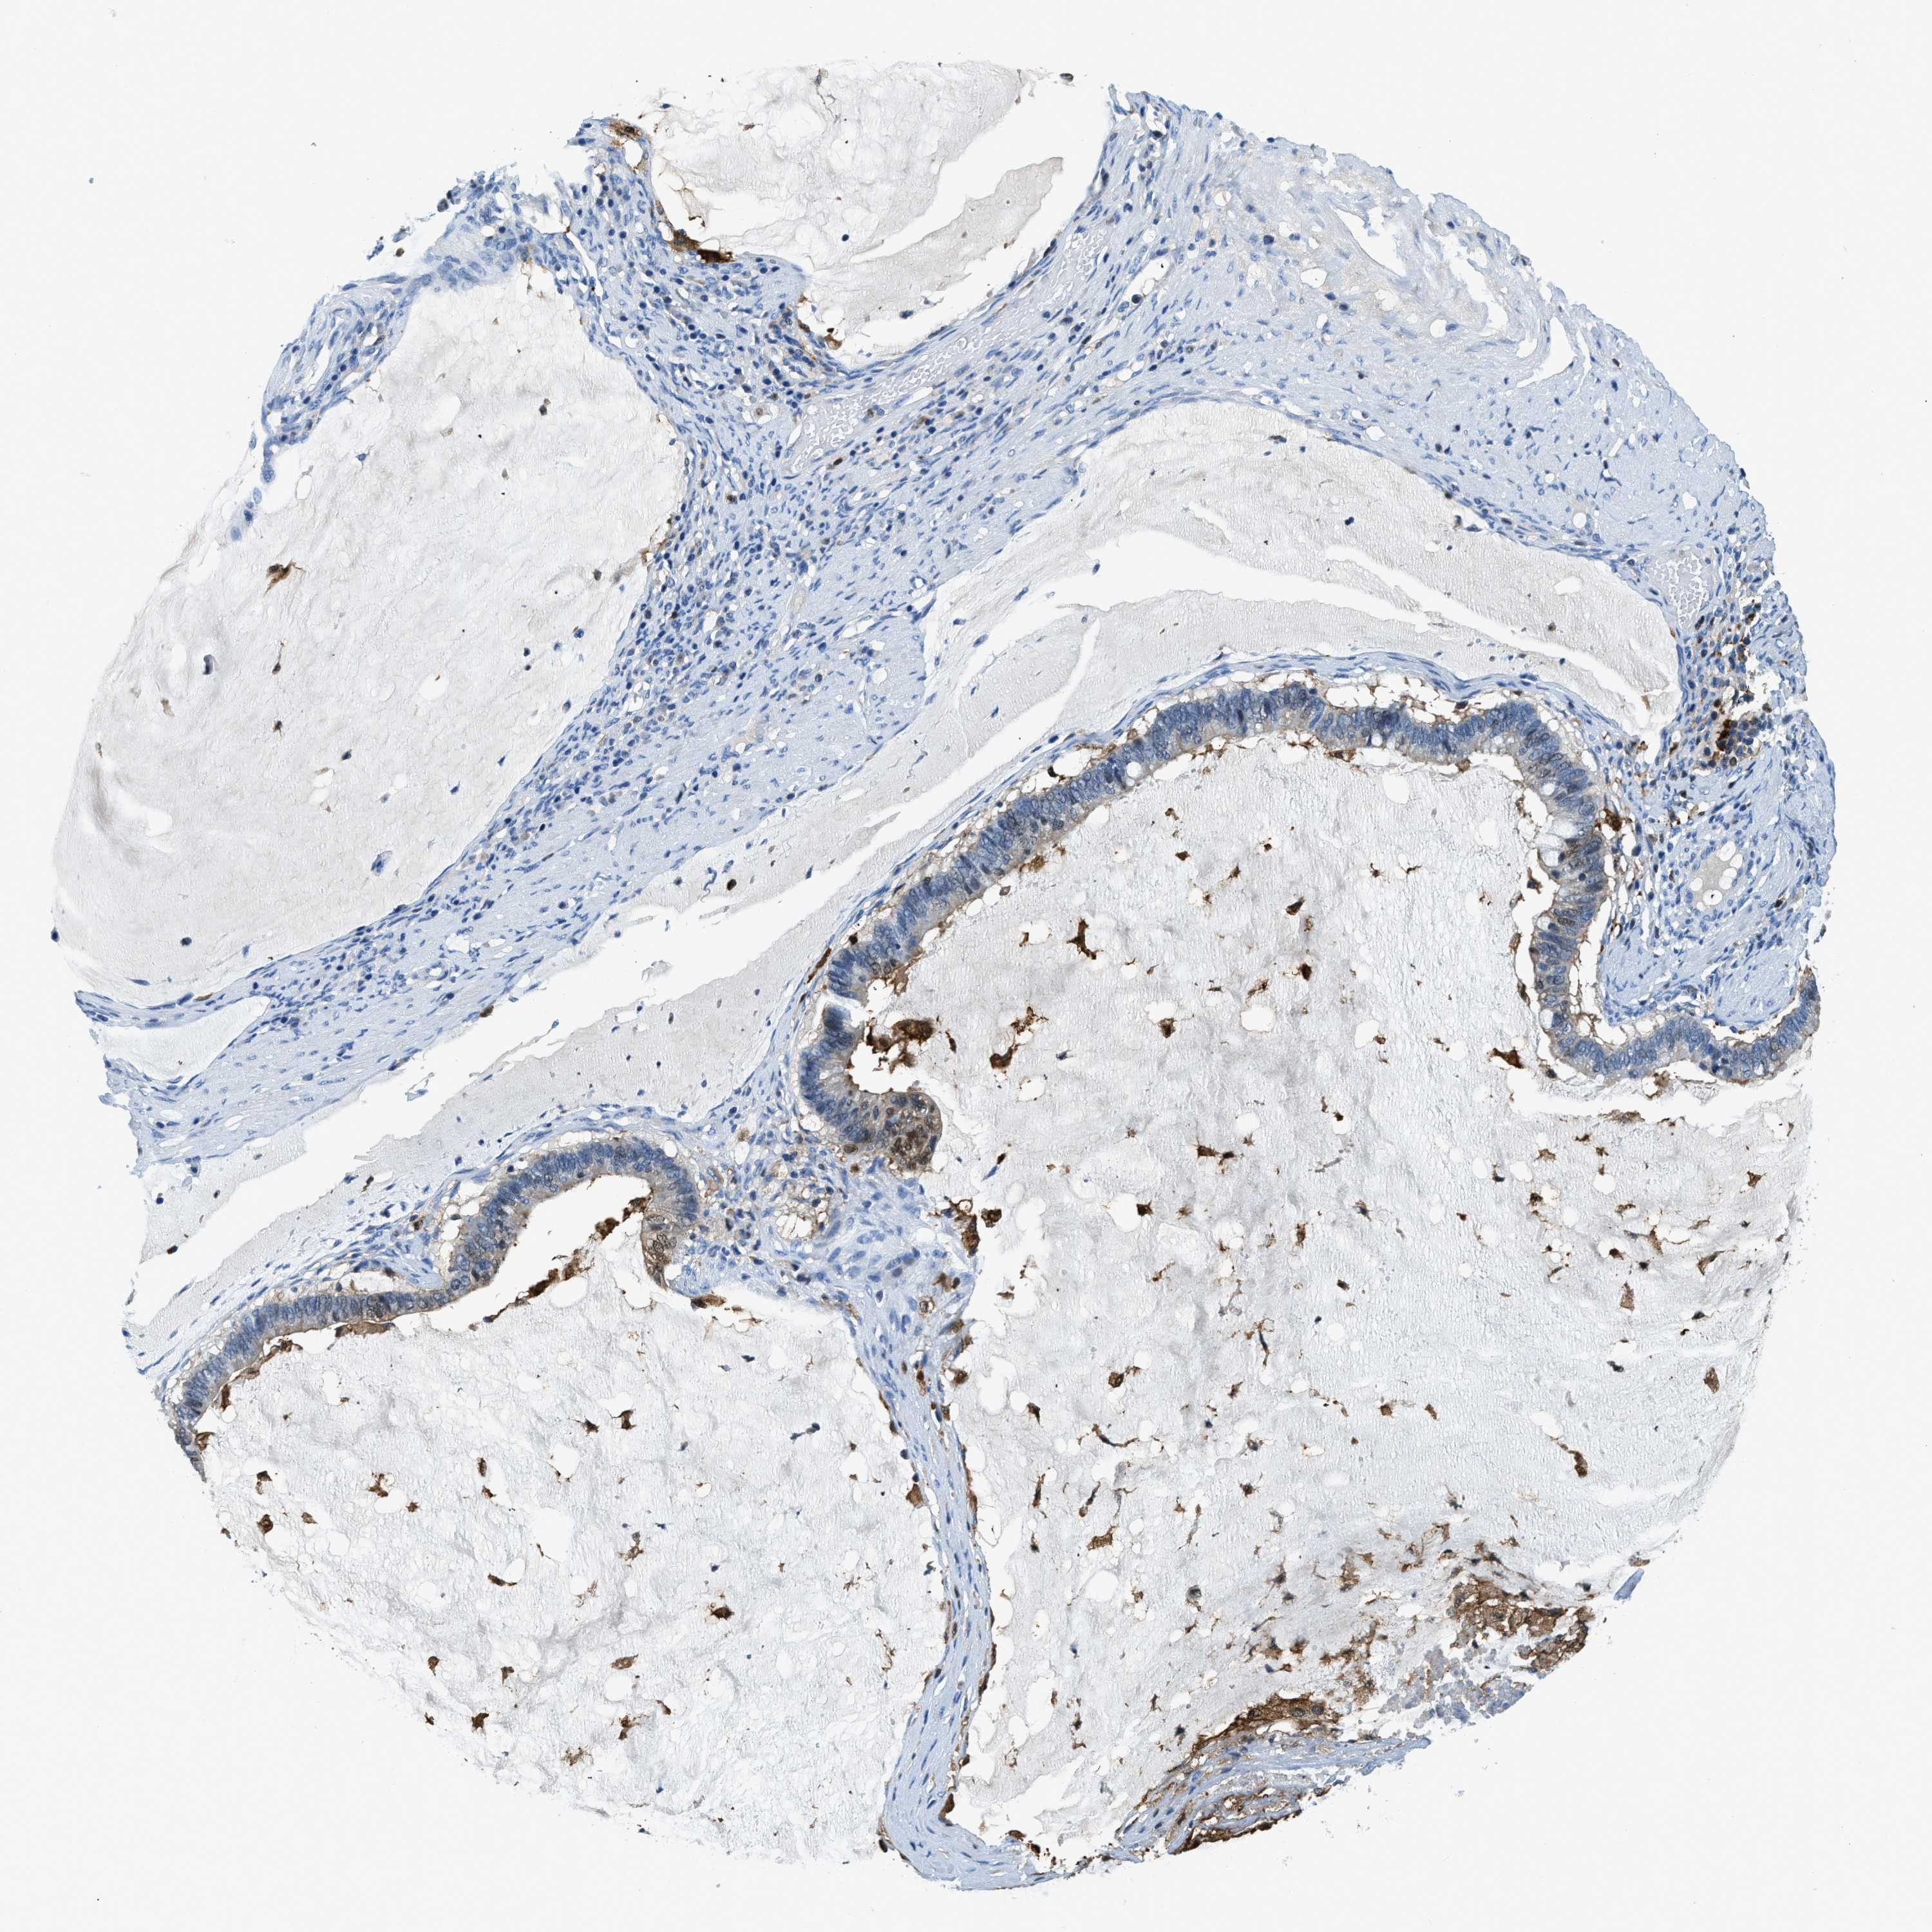

OVARIAN CANCER - Protein expressioni

A mouse-over function shows sample information and annotation data. Click on an image to view it in a full screen mode. Samples can be filtered based on level of antibody staining by selecting one or several of the following categories: high, medium, low and not detected. The assay and annotation is described here.

Note that samples used for immunohistochemistry by the Human Protein Atlas do not correspond to samples in the TCGA dataset.

Antibody stainingi

Antibody staining in the annotated cell types in the current human tissue is reported as not detected, low, medium, or high, based on conventional immunohistochemistry profiling in selected tissues. This score is based on the combination of the staining intensity and fraction of stained cells.

Each image is clickable and will lead to virtual microscopy that enables deeper exploration of all samples and also displays staining intensity scores, fraction scores and subcellular localization as well as patient and tissue information for each sample.

Antibody HPA018843

Antibody HPA019080

Antibody HPA019092

Staining

High

Medium

Low

Not detected

Intensity

Strong

Moderate

Weak

Negative

Quantity

>75%

75%-25%

<25%

None

Location

Nuclear

Cytoplasmic/membranous

Cytoplasmic/membranous,nuclear

Cystadenocarcinoma, serous, NOS

Carcinoma, endometroid

Cystadenocarcinoma, mucinous, NOS

Carcinoma, NOS